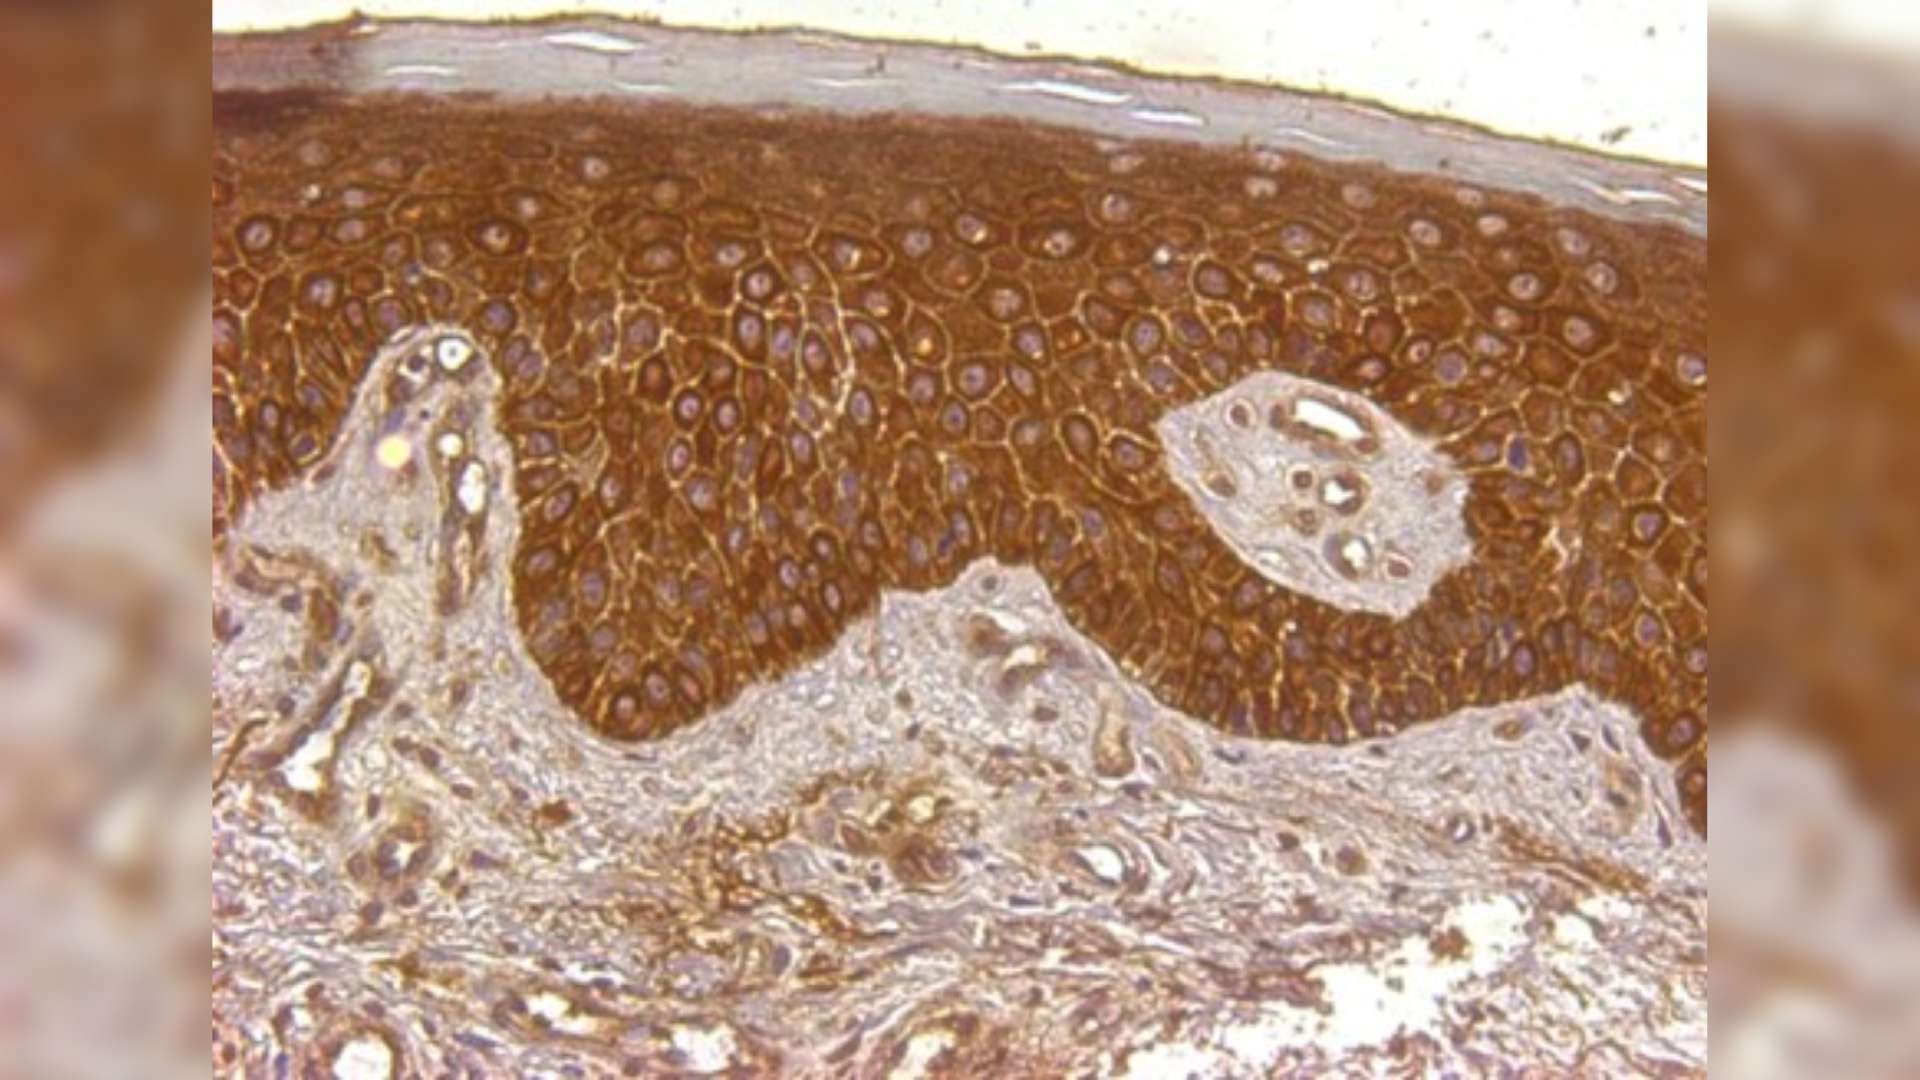

Présence d’hepcidine (visualisée en marron) dans l’épiderme d’un patient souffrant de psoriasis pustuleux.

L’équipe[1] a d’abord montré que l’hepcidine était exprimée dans la peau des patients atteints de psoriasis, particulièrement dans les formes sévères comme le psoriasis pustuleux, qui se caractérise par une accumulation d’un type de globules blancs – les neutrophiles – au sein de l’épiderme.